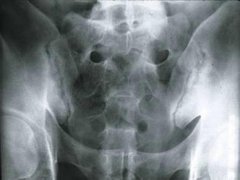

• 昔日旧病留下隐患诱发强直性脊柱炎

患者魏先生无明显诱因出现腰痛症状,经当地医院确诊为感染型强直 ...